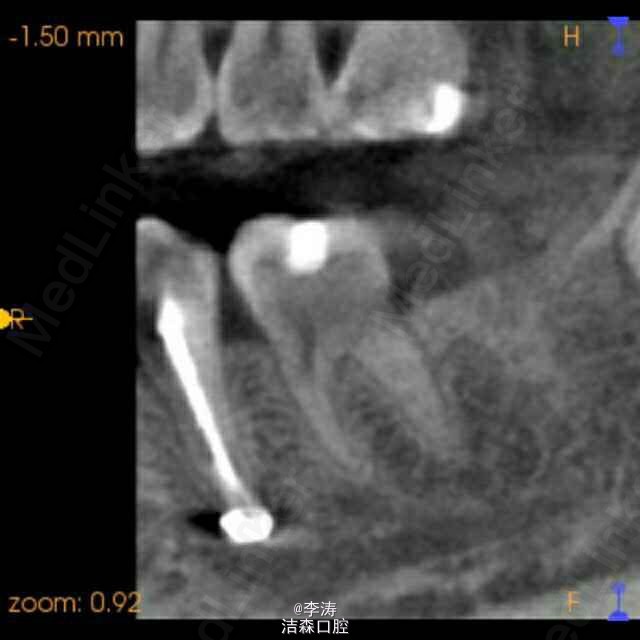

根管超填至颏孔一例,想要救你不容易!!!

遇一病人女性,20岁左右,两年前于外院35牙根管治疗,超充,正好超充于颏孔部位,患者现在还没有神经症状。该怎么补救?根尖手术,还是根管再治疗?或者有没有什么好办法?如果持续留在颏孔里面,久了会不会对神经产生什么影响?比如麻木???